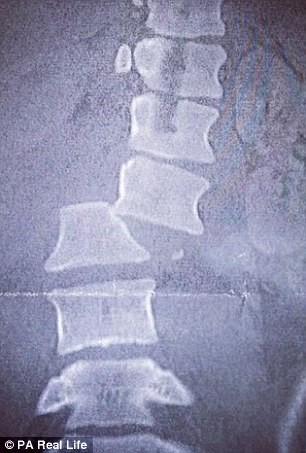

При ужасното падане девойката и счупила двете ключици, 6 ребра и гръбнака. Сблъсъкът с пътния знак й причинил множество травми на женските органи, а тялото й било парализирано от гърдите надолу. Мнозина на нейно място щяха да изпаднат в отчаяние, но Меган не се предала.

Нещастното момиче преживяло множество операции. Специалистите й закрепили гръбнака с метални скоби и успели да възстановят донякъде увредените й органи. Така Меган започнала отново да идва в спортната зала, но сега в инвалидна количка. Всеки ден тя полагала неимоверни усилия да започне да става отново и направила първата крачка.